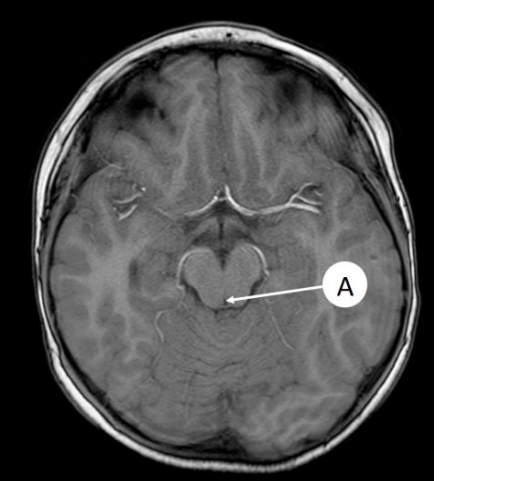

Thalamus Dex.

nucleus lentiformis dex.

capsula interna sin.

ventriculus lateralis dex.

septum pellucidum

Insula Dex.

ventriculus III

komora III